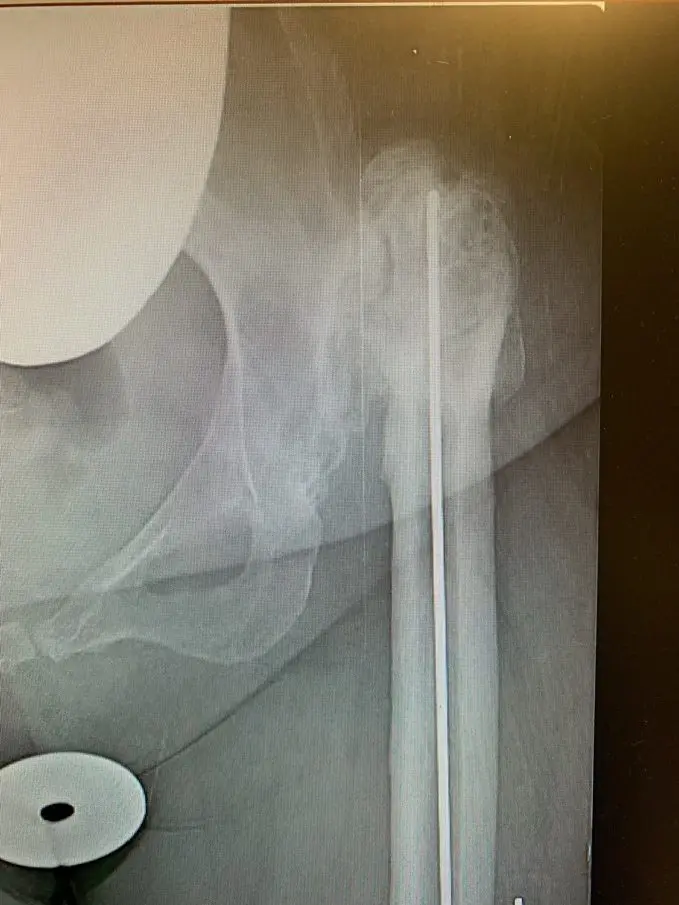

Plain film radiographs revealed a significantly arthritic hip with dysplastic features on both sides of the joint. Her contralateral hip revealed similar findings, but of lesser severity.